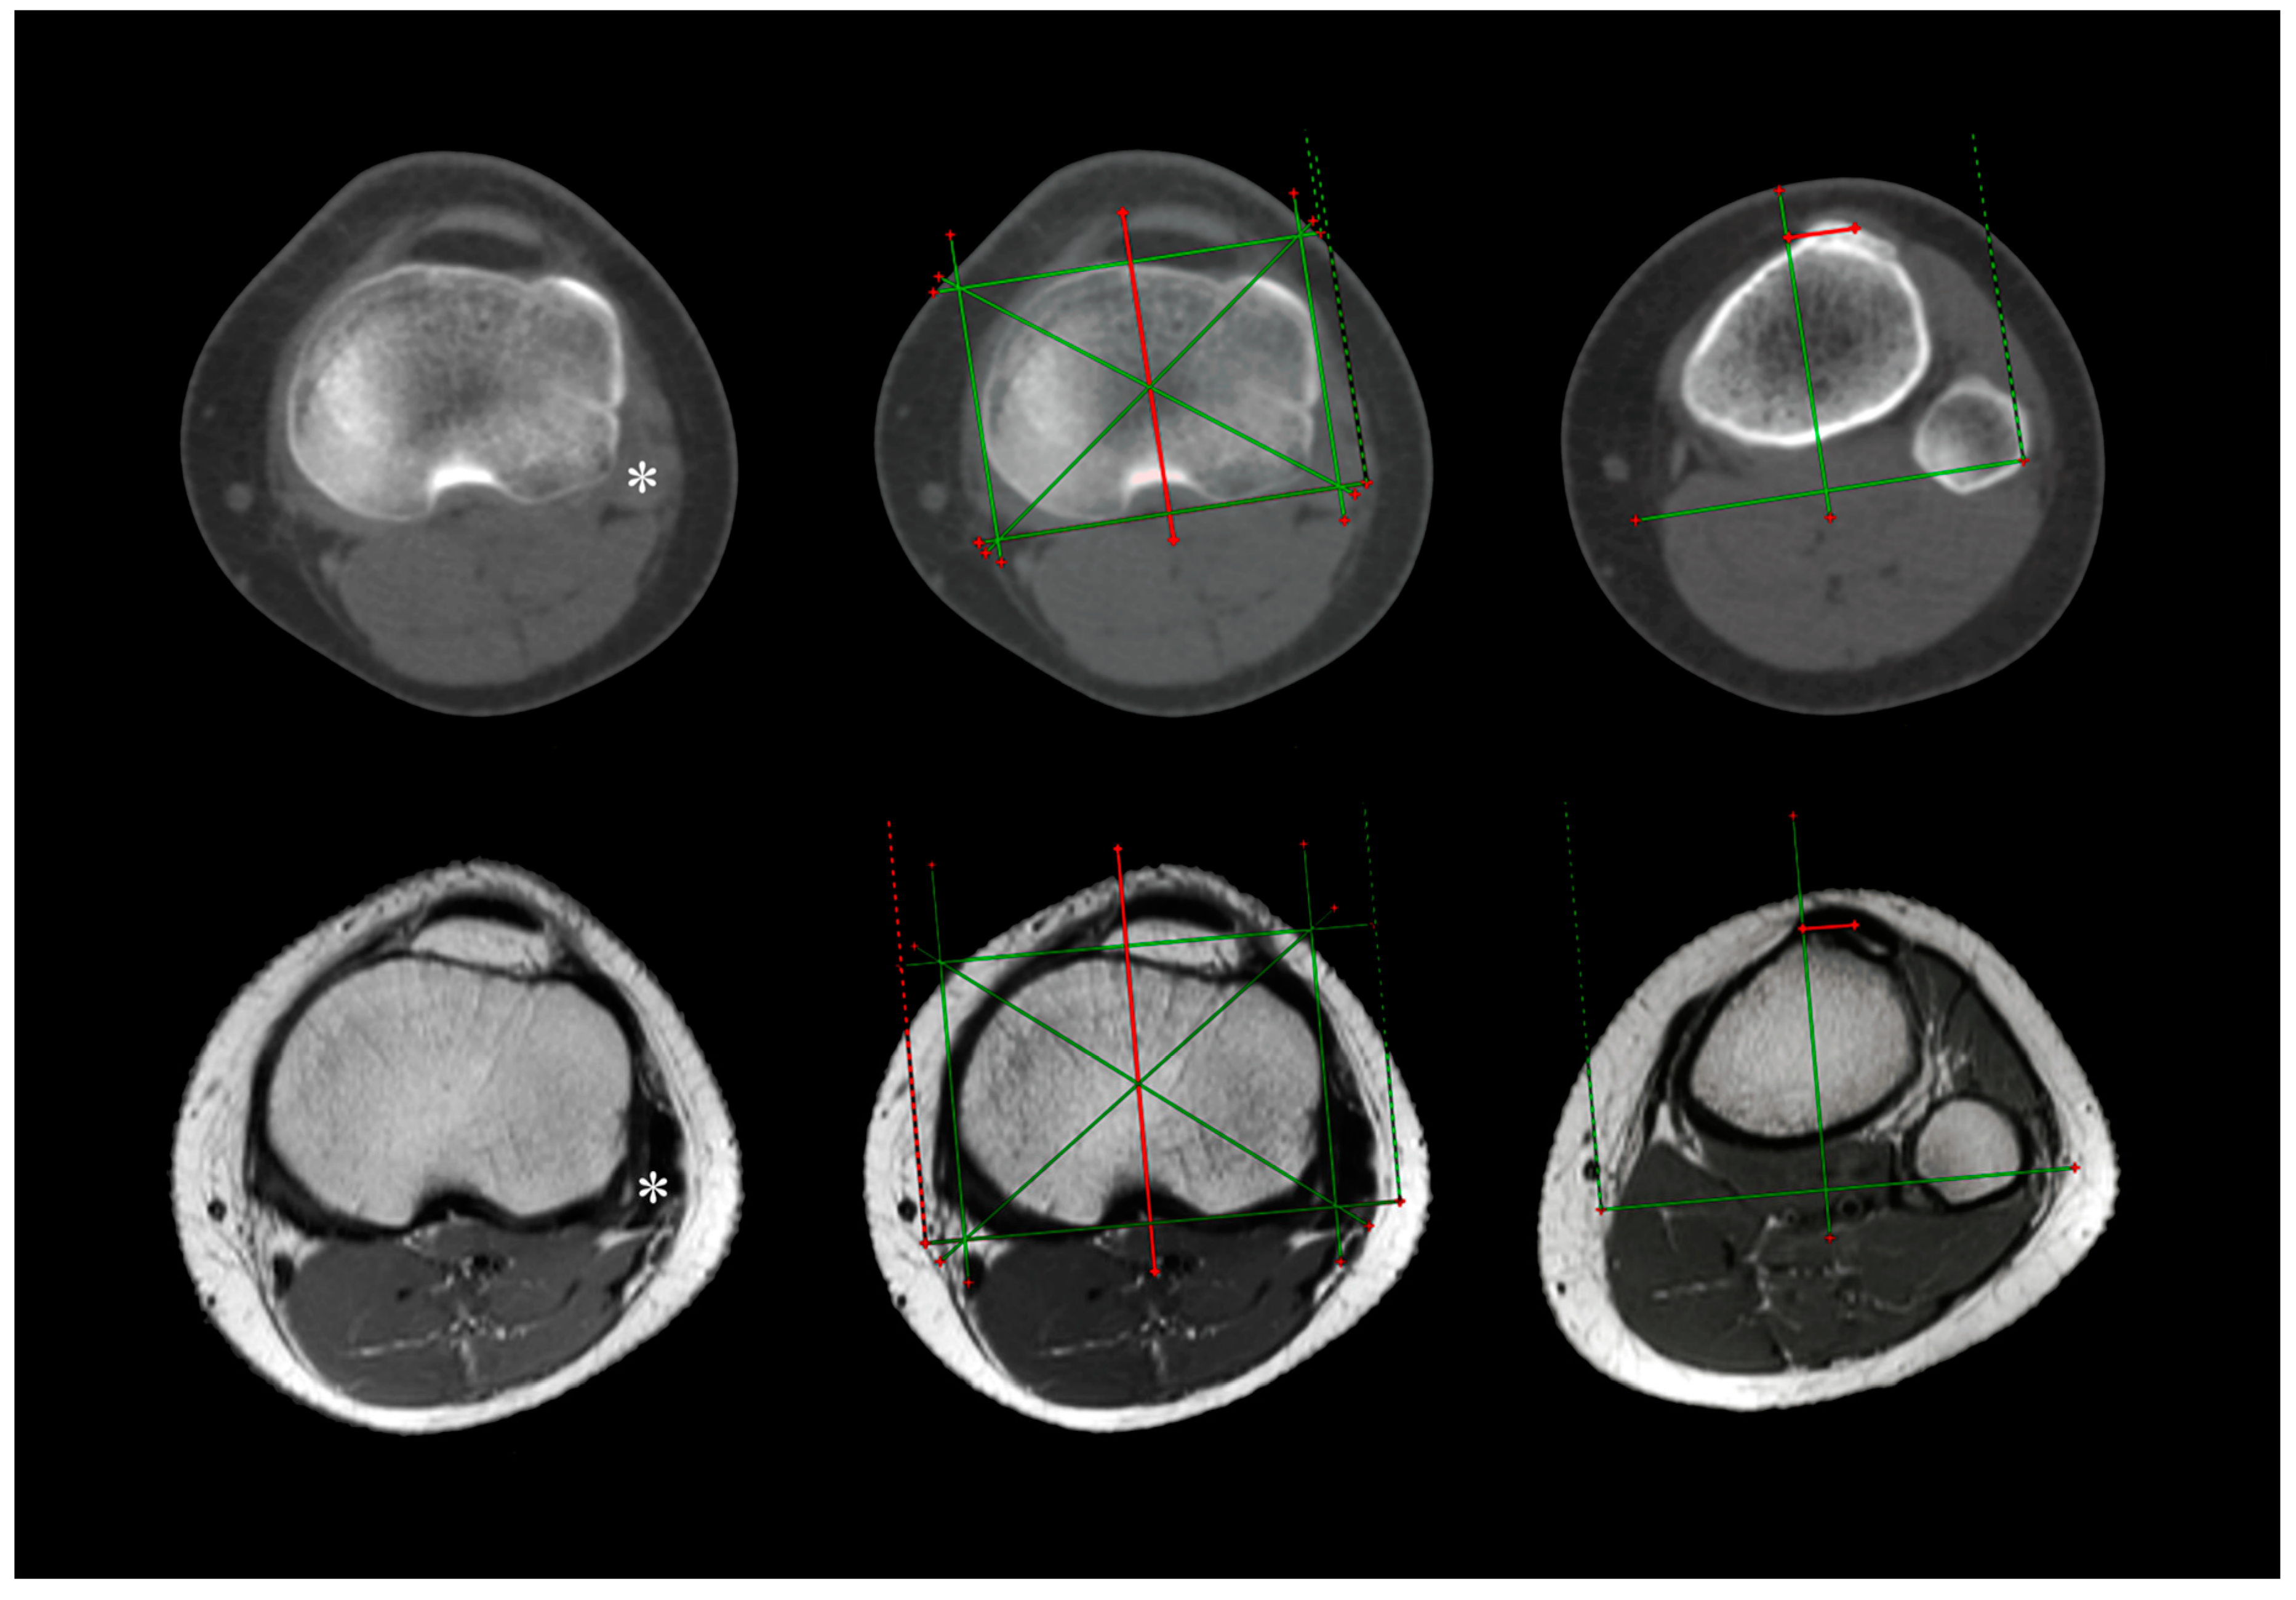

2. Materials and Methods